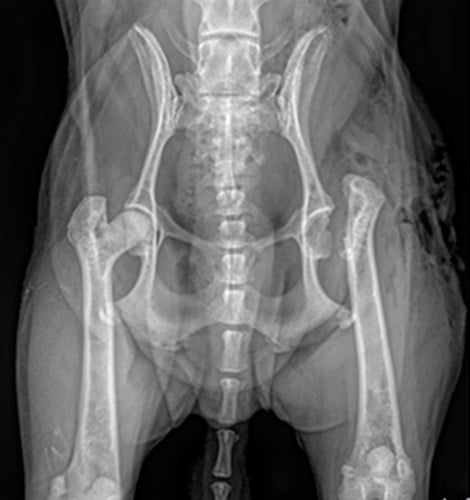

대개 고관절이형성에서 또는 이형성 때문에 생긴 퇴행성 관절염이 있는 환자에서 실시합니다.

기존의 FHNO(대퇴골두목 절제술) (왼쪽사진)과 비교하여 THR(인공 고관절 치환술은)은 해부학적구조와 기능을 회복시켜,

정상에 가까운 보행과 활동성을 기대할 수 있으며 재활의 필요성도 적고, 대형견에서도 좋은 결과를 얻을 수 있습니다.